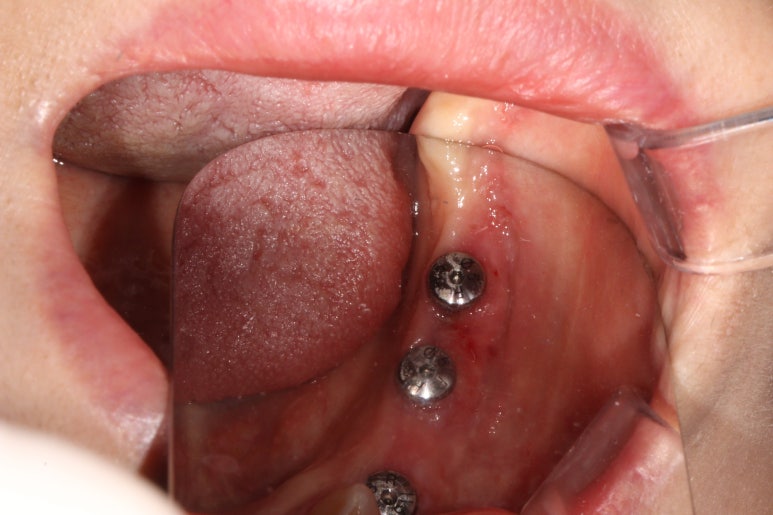

임플란트 2차수술 (3달 경과 후)

- 유리치은이식술 (free ginigval graft)

임플란트 1차수술을 마치고 정확이 3개월 뒤에 임플란트 2차수술을 시행하였습니다.

임플란트 2차수술을 하는 바로 이 시기가 유리치은이식술 (FGG)을 하기에 가장 좋은 시기입니다.

유리치은 이식술 후 봉합사 제거

약 2주 후 치유 경과입니다.

처음보다 훨씬 조화로운 색을 갖고 있고, 특이하게도 이식한 입천장 시편은 더 빨간듯한 모습을 보여줍니다.

왜냐면 재혈관화가 이루어지고 있기 때문입니다.!!

잇몸이식수술을 하고, 실밥을 제거하고 약 2주일 뒤에 임플란트 인상채득을 시행하였습니다.